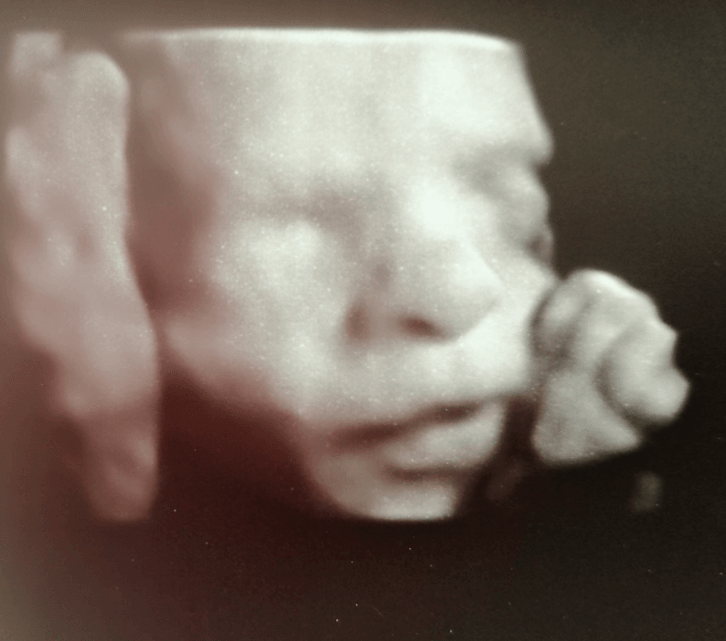

Najpiękniejsze kciuki ever!!Cześć Ciotki

Zobacz załącznik 854400

Który to tydzień?? I to jest USG 3d czy 4d ?Cześć Ciotki